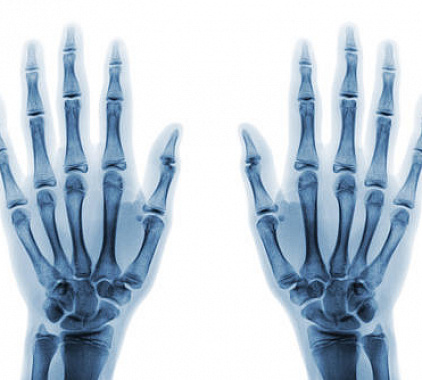

Рентген кисти в норме:

- структура, форма и размер мелких и крупных костных структур в норме;

- контуры костей четкие, ровные;

- соотношение суставных поверхностей не изменено;

- суставная щель не расширена и не сужена, имеет нормальные значения;

- повреждения и травмы не визуализируются;

- опухоли, аномалии развития и иные патологии отсутствуют.